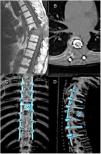

The main goal of treatment in spinal metastatic patients is local control of the disease, pain relief and the maintenance of ambulation. Traditionally, wide surgical resection of the tumour followed by adjuvant radiation and/or chemotherapy has been recommended. Currently, single-fraction or hypofractionated stereotactic body radiation therapy (SBRT) yields a one-year local control rate of over 95% with minimum morbidity, even for tumours previously considered radioresistant. In addition, by posterolateral and circumferential decompression and stabilisation of the spinal cord, it is feasible to create a 2–3mm epidural margin between the dura mater and the tumour (separation surgery), enough to deliver safe and ablative doses of SBRT to the vertebrae. As these patients tend to be frail, such interventions should ideally be minimally invasive, thereby reducing surgical aggressiveness and helping to minimise the delay of any systemic therapies.